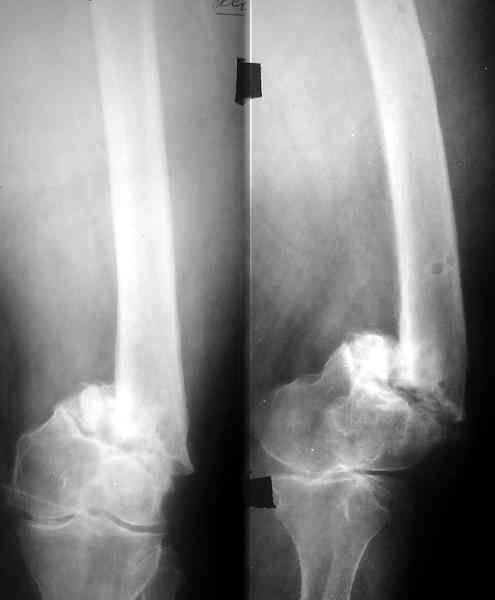

По всей вероятности, после перелома бедренной кости, случившегося 15 лет назад, у больной сформировался псевдоартроз в дистальной эпиметафизарной зоне. Травма этого года привела, с моей точки зрения, к частичному разрушению псевдоартроза, а не к повторному перелому. Учитывая амнестические данные о больной, я бы не спешил с оперативным вмешательством, а предложил бы больной съёмный ортез и нагрузку на ногу в течение двух-трёх месяцев. Такой промежуток времени при данной патологии не ухудшит условия для оперативного вмешательства, если оно потребуется, но позволит более определённо установить необходимость такового, если конечность не станет опорной или больная сама станет настаивать на оперативном вмешательстве.

Что касается самого оперативного лечения, то оно представляет значительные трудности и положительный исход его не столь очевиден. С моей точки зрения, адекватная фиксация любой металлоконструкции в дистальном отломке бедренной кости невозможна. Поэтому вариантов вмешательства два: либо ВКДО с фиксацией голени (что, учитывая конституцию больной и сопутствующую патологию, менее приемлемо), либо антеградный БИОС с прохождением стержня через коленный сустав и дистальным блокированием в проксимальном эпиметафизе большеберцовой кости. И в том и другом случае потребуется открытая репозиция и костная пластика (возможно в несколько этапов). Вопросы восстановления длины конечности и функции коленного сустава на данном этапе лечения не главные. Цель оперативного лечения – восстановление опорной функции конечности и сращение перелома.

Пример подобного ложного сустава в приложении.